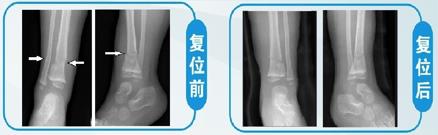

(2)踝部骨折 由于骨折靠近关节,若手术治疗对踝关节周围韧带等软组织损伤很大,容易造成术后关节功能恢复不良。科室对这类骨折有独特的复位和固定方法,复位理想,关节功能恢复良好。